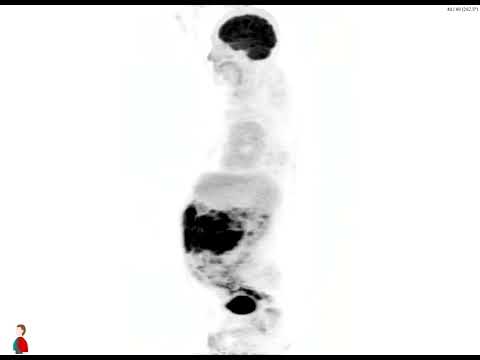

Case Challenge: # 57

Test your skills by providing answers in comments. Come back to check the answer key in 24 -48h.